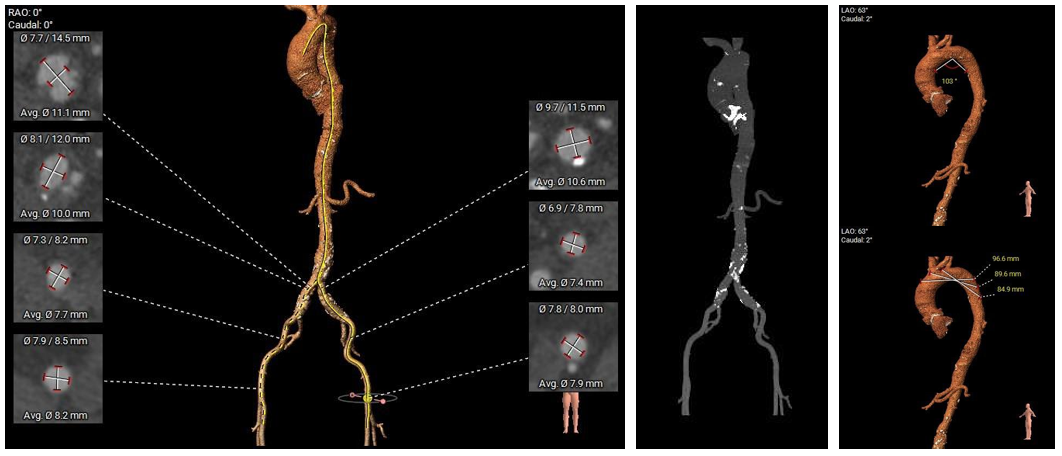

术前CT评估

●主动脉瓣生物瓣置换术后,生物瓣瓣叶未见明显血栓,人工瓣膜瓣架周围未见明显纤维组织增生;左室流出道呈敞口型;

●左右冠开口高度尚可,生物瓣架不高;冠脉散在钙化;

●瓦氏窦、窦管交界、升主动脉内径尚可,左室腔内径尚可,心室壁未见增厚;

●主动脉瓣环与水平面夹角为52°,主动脉弓宽度、角度尚可;

●主动脉弓、腹主动脉、双侧髂总动脉可见散在钙化斑块,右髂总动脉似可见局部溃疡,入路血管直径尚可。

主动脉根部测量

瓣上结构测量

冠脉阻挡风险及左室大小评估

外周血管入路评估